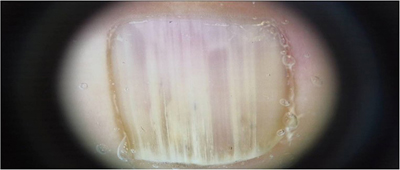

Onychopapillome (figure 1)Parmi les diagnostics différentiels de l’onychopapillome il faut désormais compter :– l’acanthome du lit [1] (ou nommé également kératose séborrhéique) avec des présentations variables : mélanonychie avec hyperkératose du bord libre, grains de milium, xanthonychie, leuconychie ou érythronychie plus rares. La figure ci-dessous monte le cas d’un patient de 54 ans. Le diagnostic différentiel principal dans ce cas reste la maladie de Bowen.– l’onychopapillome malin, publié par [...]